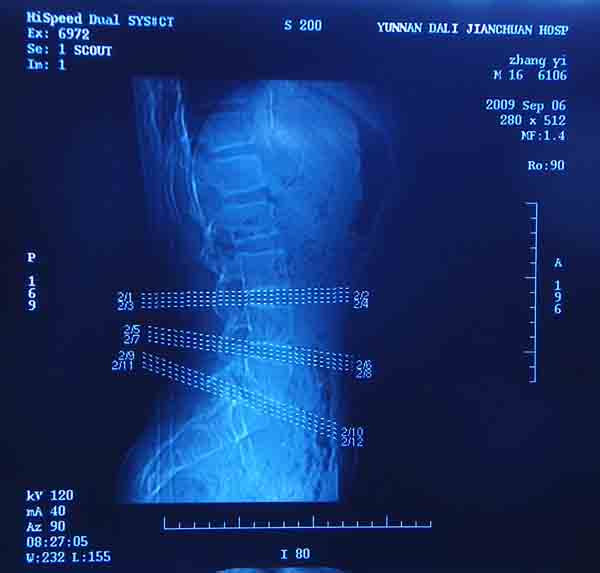

腰5/骶1椎间膨突出外,还有点异常,不知是什么东东,请各位大虾帮忙看看(12骨窗最明显)